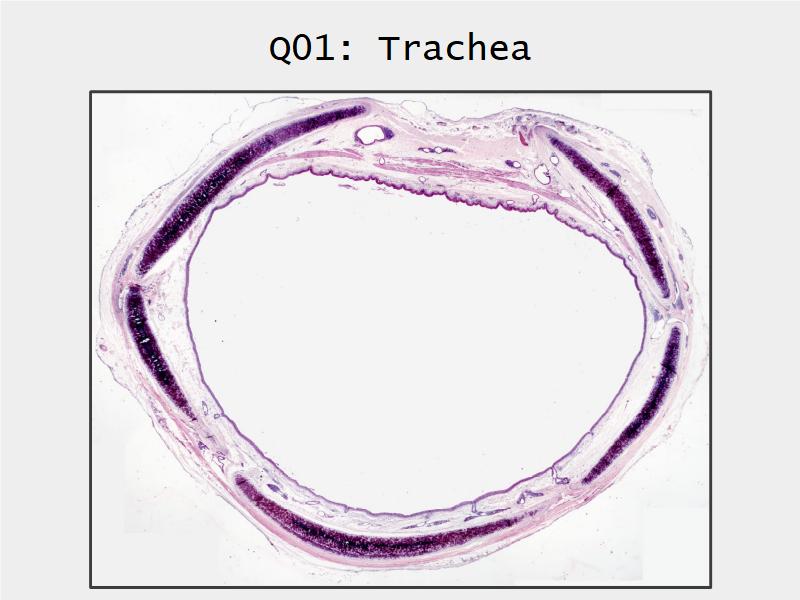

Respiratory Epithelium: Trachea

Today and Now I will do something for my future self.Trachea

- Slide 73: Trachea

Respiratory epithelium

- Pseudostratified

- Ciliated

- Columnar

- Epithelium with

- 4 Cells

- Ciliated columnar cells

- Non-ciliated columnar cells

- Goblet cells

- Basal cells